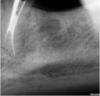

ARislanV Опубликовано 14 июня, 2012 Поделиться Опубликовано 14 июня, 2012 Взялся за перелечивание 36 зуба, работал долго и усердно, но результат разочаровал.36 зуб. Ранее лечен резорцин формалиновым методом, перкуссия и зондирование без болезненно.Использовал УЗ и стальные инструменты, в общей сложности на работу ушло 5 часов времени. Расширял до 35 номера, пломбировал латералка и АН+.Сейчас планируется динамическое наблюдение, ВКВ и коронка.Каков по вашему прогноз у зуба и что бы вы могли посоветовать? ) Ссылка на комментарий

igorstom Опубликовано 14 июня, 2012 Поделиться Опубликовано 14 июня, 2012 Не соглашусь, если после ретрита наблюдается положительная динамика, то при адекватном протезировании можно с большой долей вероятности говорить о благоприятном прогнозе.Вдруг там перфа, или просто обострение в ближайшем будущем будет? Зуб не удалось хорошо переделать, рентгенологическая картинка явно не располагает к хорошему настроению, так зачем еще больше усугублять финансовый вопрос протезированием? Куда спешить, на пожар что ли? Информирование согласие не поможет, если нарушаются медицинские показания и противопоказания. Вы готовы от своего имени утверждать, что этот зуб по всем статьям подходит под протезирование и риски минимальны? А если нет, то напишите на каком основании его короновать, если он при определенном взгляде просится на удаление? Чтобы уж не волноваться- тогда удалять и имплант.Ну, Kivilgar, не забывайте, что мы иногда работаем для различных групп населения. Если Вы работаете в дорогой клинике по бешенным ценам - то конечно, Вы и рассуждаете совсем по другому. Но представьте, что качественное лечение Вы не можете делать в силу того, что зуб до Вас уже запортачили совдеповскими методиками. А у пациента денег на имплант нет, да и не будет он его ставить в силу сложившегося менталитета ("всё равно не приживаются"). Как быть тогда?У нас на Урале 80% врачебного персонала составляют зубные фельдшера (язык не поворачивается назвать врачом со средним образованием). И резорциненные передние зубы, и перфорации, сплошь и рядом. У нас даже зубные техники в деревнях "пилят" зубы. Понимаете, куда я клоню?http://s56.radikal.ru/i151/1206/f1/7e5b14a35884t.jpghttp://s43.radikal.ru/i101/1206/5b/a78b1c0e3243t.jpg 1 Ссылка на комментарий

ARislanV Опубликовано 18 июня, 2012 Автор Поделиться Опубликовано 18 июня, 2012 так все обычно) берете эндомотор, новые машинные инструменты ... и распломбировываете ими в методике краун даун клюющими движениями. ... у вас же в каналах паста, может она конечно и рф, но насмерть прорезорциненным он не выглядит...УЗ для ретрита можно полностью работать в прямых каналах, либо для создания доступа к изгибу под контролем оптики. а в таких каналах, без больших увеличений, max аккуратно в устьевой части размягчить материал, если очень плотно, а потом машина - либо пройдет, либо нет. но чаще проходит.В каналах резорцин. На снимке мед. каналы запломбированы порами, на деле же оказалось что они запломбированы очень плотно. Дистальный канал, на против, на снимке виден что заплоибирован как "бетоно-непробиваемый", на практике дался легче всех остальных.С пастами обычно проблем не вазникает, обрабатываю стальными и переодически по мере прохождения вымываю УЗ. Роторными боюсь зделать ступеньку. В любом случае уже трогать зуб бесполезно. Еще один ретритмент он не выдержит.Но будет вам как небольшой урок на тему НЕОБХОДИМСТИ ретритмента асимптомного рф.Да каждый такой случай дает много опыта и пищи для размышлений. И если бы я знал что такой будет результат, я бы не наченал лечения.Но в будещем будет еще много таких асимптомных рф. На фотографии этого зуба видно, что пломба занимает всю оклюзионную часть, после удаления этой пломбы остаются тоненькие стеночки(аналогия с фарфоровой чашкой). Тактика восстановления коронковой части это ВКВ и коронка. А что бы ортопед смог зделать туда вкладку терапевту(т.е. мне) нужно подготовить каналы. Поэтому я прелагаю все усилия для их перелечивания. В 40%случаях мне удается пройти каналы и запломбировать их до верхушек. В 30% мне удаеться улучшить ситуацию и в 30% это не удача(как в этом случае). А какую "химию" Вы использовали при распломбировке?Раньше пробовал Энодосольфы, гели. Но помоим ощющениям они не дают ни какой помощи, а только морально сбивают с толку т.к. дают не оправданные надежды. (кто то говорил что "царская водка" помогает)А чем работаете вы? Может у вас есть положительный опыт и вы посоветуете мне что нибудь . ... что в РФ зубах долгое отсутствие клиники связано как с зачастую ярко выраженным склерозом апикальных отделов корня (что препятствует доступу токсинов в периапекс), так и с устоявшимся хрупким балансом как между ослабленными микроорганизмами внутри канальной системы, так и между ними и иммунной системой. Поэтому как и подготовка к протезированию так и просто изменение жевательной нагрузки после ортопедии не перелеченного РФ, может вызвать разрушение устоявшегося хрупкого равновесия, что приводит зачастую к обострению периодонтита после протезирования зуба, ранее себя никак не проявляющего.Не давно был на семинаре у Болячина Алексея Вячеславовича, он также расказывал про хрупкое равновесие в каналах между микроорганизмами и имунной системой. И если кто то захочет сделать ВКВ на такой асимптомный рф без попытки перелечивания, а только распломбировав один канал на 2/3 под ВКВ. Он тем самым "вскрывает ящик пондоры", может повести, а может дать обострение через пол годика и тогда зуб в месте с ВКВ и коронкой в плювашку.Поэтому считаю, что терапевт должен сделать все, что может. Если каналы пройдены не до конца, тогда ту длину на которую прошли по максимуму отмываем, расширяем и пломбируем на постоянную. Коронковую часть герметично закрываем и проводим динамическое наблюдение. Т.е. вызваниваем через 6 месяцев делаем R снимок, если рентгенологическая картина спокойная, продолжаем наблюдение. Вызваниваем еще через 6 мес. делаем R снимок. Если без изменений, тогда протезируем ВКВ и коронка. Ссылка на комментарий